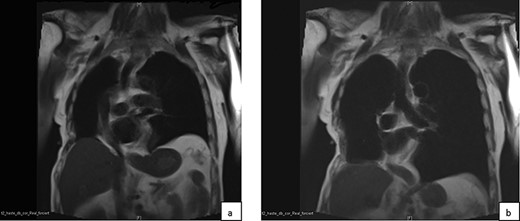

In dynamic magnetic resonance imaging examination of the thorax in coronary view in end-expiration (a) and end-inspiration (b) a paradox movement of the reconstructed area of the chest wall is observed.

Three years after surgery, a dynamic magnetic resonance imaging examination and a lung function testing were performed in order to evaluate the long-term effects of the technique used on the stability of the chest wall and its functional relevance [4]. Paradoxical movement on the reconstructed side was observed there but there was no clinical or radiological evidence of relevant functional impairment (Figs 2 and 3). Pulmonary function showed an FEV1 of 60%, VC of 79% and a DLCO cSB of 70% of predicted value. The patient suffered from slight residual pain in the operated region with mild dysaesthesia. He describes his quality of life as very good.

The result 3 years after surgery in expiration (a) and deep inspiration (b) demonstrates a paradox movement locally.